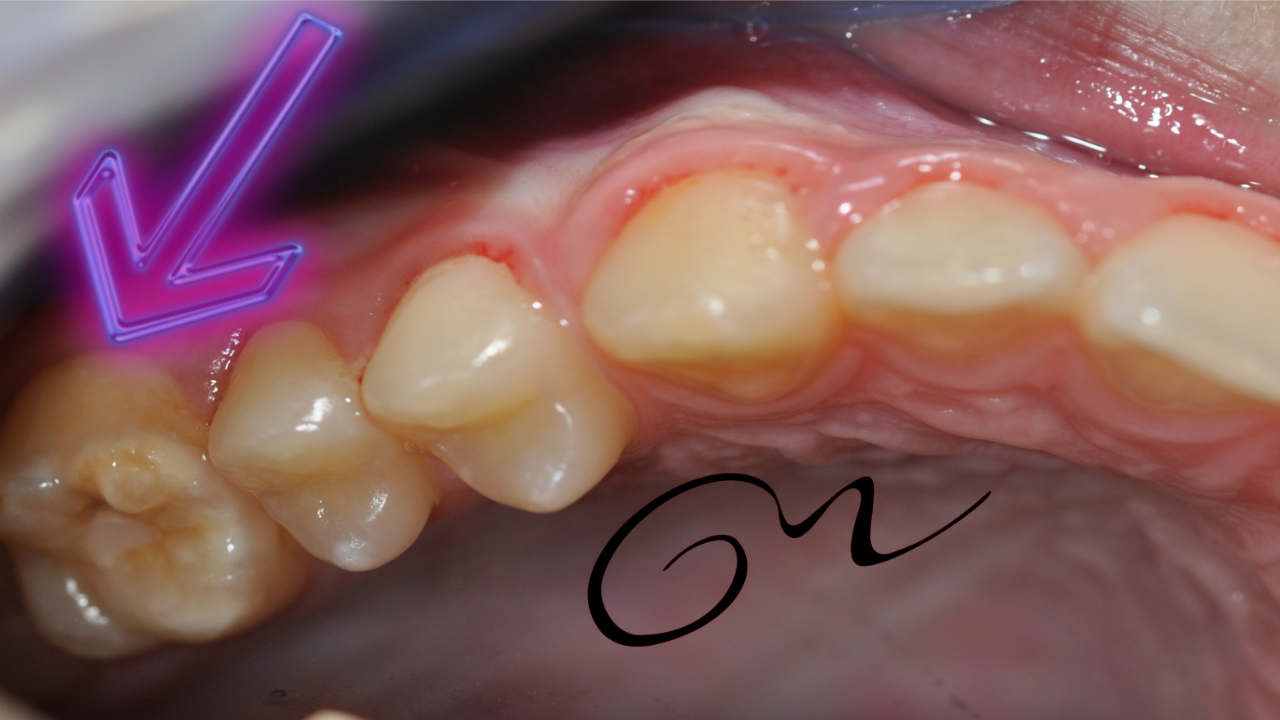

- Grado 2: Opacidades color amarillo- marrón, con afectación de cúspides, leve pérdida de sustacia y algo de sensibilidad.

- Grado 3: Deficiencia grave con defectos de corona, pérdida de esmalte y compromiso pulpar. Mucha sensibilidad por exposición de la dentina.